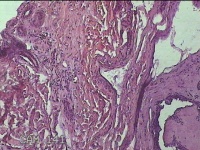

右侧颜面部结节

性别

男

年龄

49岁

临床诊断

皮脂腺囊肿

一般病史

发现右侧颜面部结节5年余。

标本名称

大体所见

灰白暗红色组织1x0.7x0.3cm一块,表面带梭形皮肤1x0.5cm,皮下见结节0.9x0.7x0.3cm一个,切开结节呈实性,切面灰白暗红色,质中。

图2